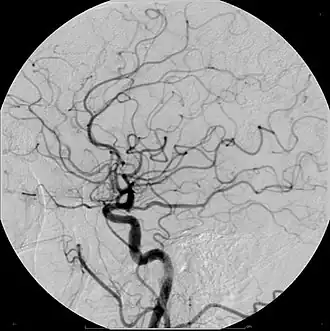

Angiograma: debido a la remodelación positiva, la acumulación de placa mostrada en el angiograma puede aparecer más adelante en la radiografía, donde el diámetro luminal se vería normal a pesar de que hay un estrechamiento severo en el sitio real. Debido a que los angiogramas requieren rayos X para ser visualizados, el número de veces que un individuo puede realizarse uno en un año está limitado por las pautas sobre la cantidad de radiación a la que pueden estar expuestos en un período de un año.